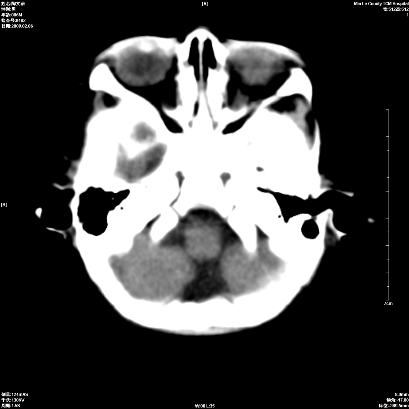

以下是引用wxq2008在2009-2-6 17:01:00的发言:[br]hie后遗症脑萎缩。

以下是引用学医在2009-2-6 21:45:00的发言:[br]hie后遗改变